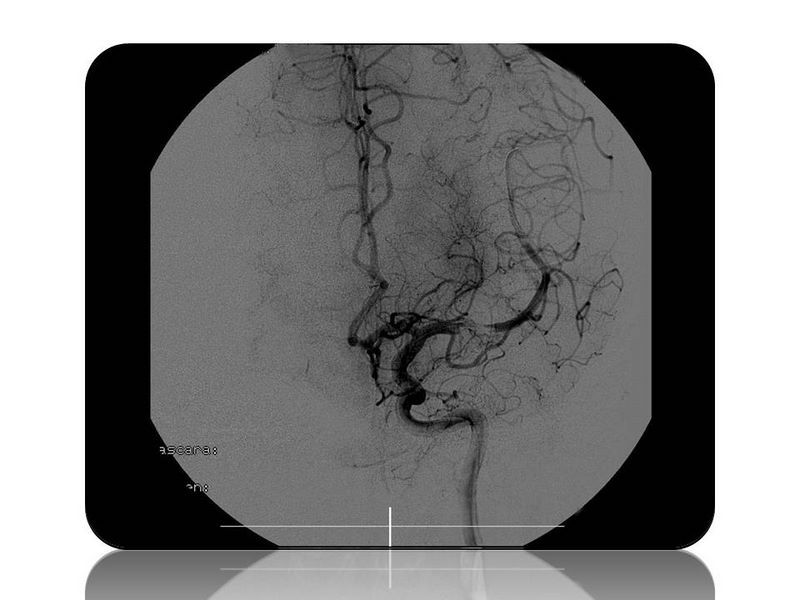

Ictus con stent